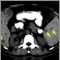

Metastasis is the movement or spreading of cancer cells from one organ or tissue to another. Cancer cells usually spread through the bloodstream or the lymph system.